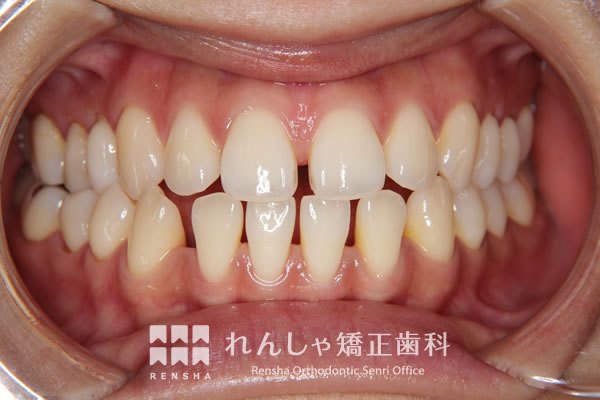

大きながたつきを歯列の拡大で改善しようとすると歯周組織へのダメージや後戻りが問題になります。この様な場合はスペースを確保するために永久歯を抜歯する方法を選択します。歯を抜いてしまうことに不安もあるかと思いますが、抜歯矯正が長い目で見たときにいい結果になることも多いと思います。

治療前

| 主訴 | 叢生 |

|---|---|

| 診断名 | Angle Class I 叢生 |

| 初診時年齢 | 27歳0か月 |

| 装置名 | マルチブラケット装置 |

| 抜歯非抜歯 | 上下顎左右第一小臼歯の抜歯(合計4本) |

| 治療期間 | 2年5か月 |

| 費用の目安 | 約93万円+消費税(検査料金、都度の処置費用等も合わせた総額) |

| リスク副作用 | 歯の移動に伴う軽微な歯根吸収、歯槽骨吸収、歯肉退縮(本症例では軽度の歯肉退縮を認めた)、矯正器具装着中のカリエスリスク増大(本症例ではカリエス発生無し) |